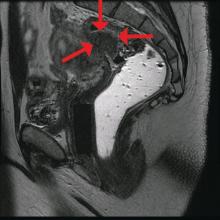

In general, there is agreement among surgeons that for consideration of discoid resection, nodule diameter should not exceed 3 cm, with a maximum of half of the bowel circumference and a maximum of 60% stenosis. I view these numbers as guiding principles, however, and not firm rules. Surgical decisions should be personalized based on the patient, the surgeon’s impression of the extent of the disease, and the ability to perform anterior discoid resection without compromising the rectal lumen with primary closure of the defect.